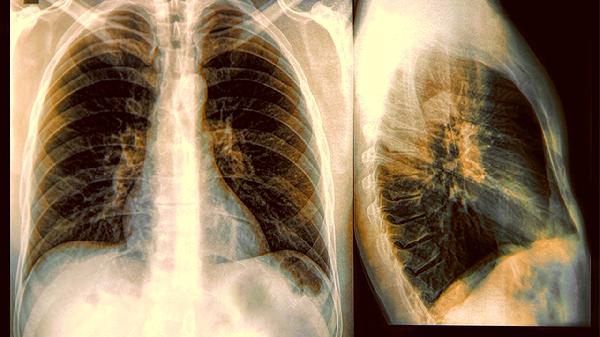

脚部皮肤无故出现苍白、发紫或片状暗沉,尤其是这种现象从脚趾逐渐向脚背蔓延时,可能是血液循环障碍的表现。某些呼吸系统疾病会导致血氧饱和度下降,足部作为肢体末端最先显现征兆。